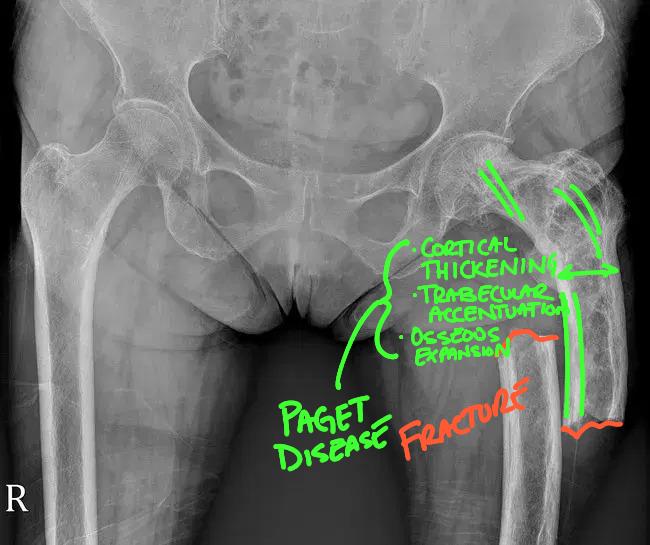

Paget Disease of Bone: A Comprehensive Guide for Chiropractors, Primary Care Providers, and Urgent Care Centers

Paget Disease of Bone: A Comprehensive Guide for Chiropractors, Primary Care Providers, and Urgent Care Centers Overview Paget Disease of

Read More